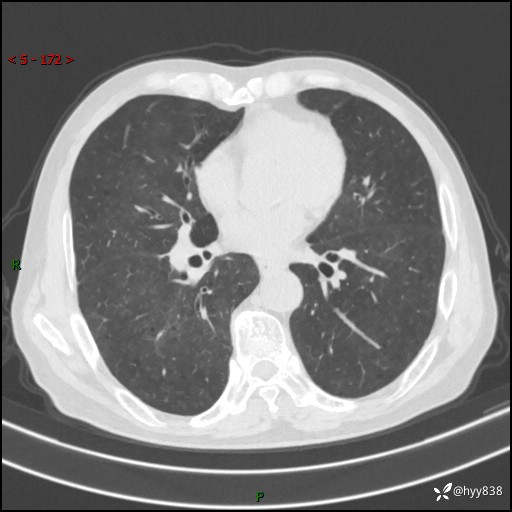

辅助检查:CT

胸部CT平扫